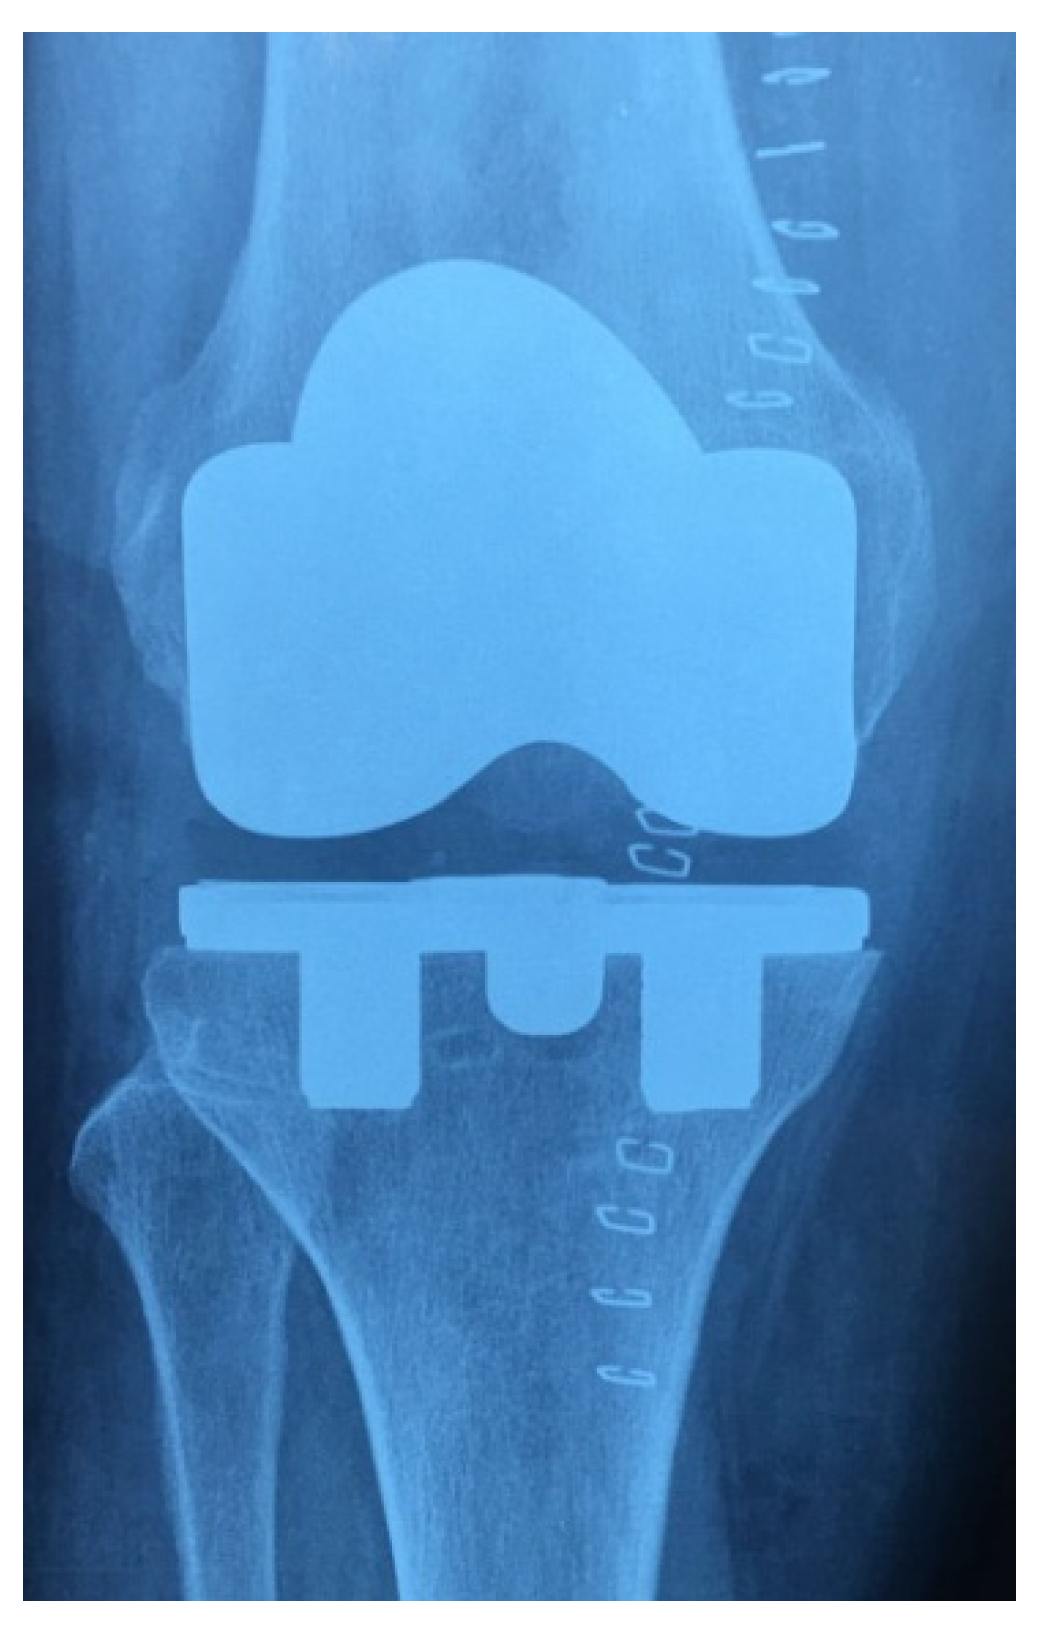

Preoperative planning was made in all cases on plain radiographs with different views: anteroposterior and lateral of the knee, weight-bearing telemetry of the affected limb, and skyline of the patella. Preoperatively, the Knee Society Score (KSS) and the Knee Injury and Osteoarthritis Outcome Score (KOOS) were submitted to the patients. All the knee arthroplasty surgeries were performed only by experienced orthopedic surgeons. In all patients, a tourniquet was inflated before skin incision, and it was released before the suture; the chosen approach was the medial parapatellar. Resections of the proximal tibia and the distal femur were performed according to the mechanical alignment concept, which aims to place the femoral and tibial component perpendicular to their mechanical axis. After establishment of the tibial cutting platform and resection of the proximal tibia, the appropriate size (i.e., the one that provides the desired bony coverage) was selected with respect to the anatomical landmarks, the holes were drilled in straight (an angulation of the holes may prevent from proper seating), and the definitive component was inserted by hammering firmly with the knee fully flexed and the tibia advanced forward. The femoral component was cemented in all cases; patellar resurfacing was never performed. Before closure in layers, one closed suction drainage was used and removed after 36 h in all the procedures. Two boluses of 10 mg/kg of tranexamic acid were administrated intraoperatively and two hours after surgery; postoperatively, all patients were given mechanical and pharmacological prophylaxis for deep vein thrombosis and underwent the same postoperative rehabilitation protocol. Weight-bearing as tolerated was permitted from day 1 after surgery. Postoperative clinical evaluations with the above-mentioned scores were performed at 1, 3, 6, and 12 months follow-up and annually thereafter; radiographs were collected at the last follow-up to identify any signs of polyethylene wear, radiolucency, septic or aseptic loosening, and change in alignment (Figure 3 and Figure 4).

Figure 4. Radiographic image of a TKA using a two-peg monoblock TMT tibial component.